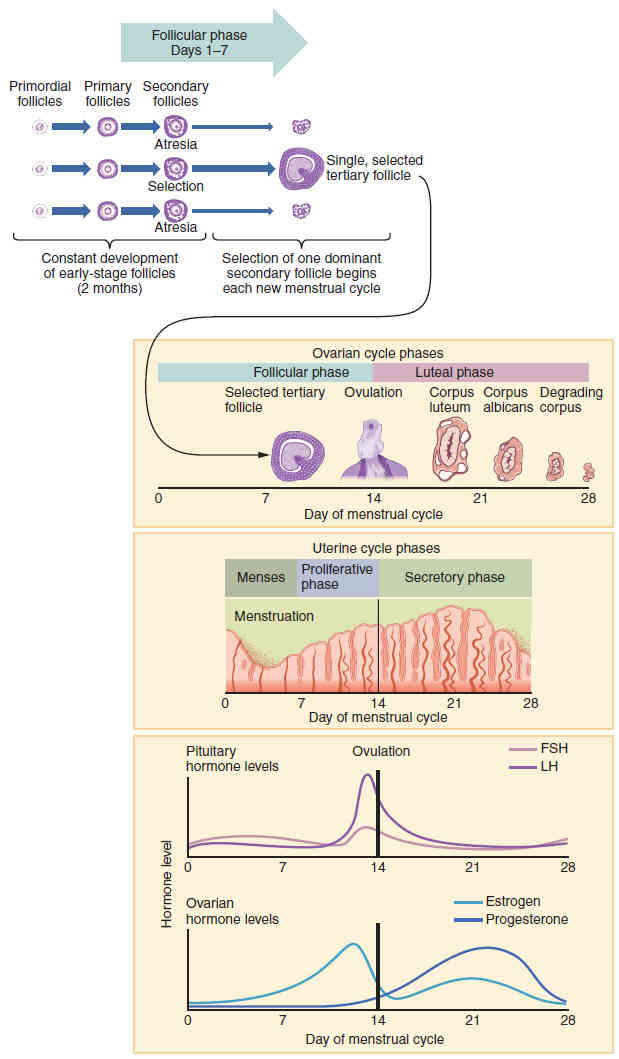

This page is under construction. For now, it is just a resource of the images found in the OpenStax Anatomy and Physiology Handbook. It wil slowly change into a revision tool. Each slide has a number. Use this to refer to the slide. When completed, it will have an unlabelled section, with labelled slides in parallel. On the unlabelled slides, write your answer and use the labelled slide to assess yourself. Keep track by also noting the number on each slide. Improvement at each attempt is important, more so than full marks on a first attempt.